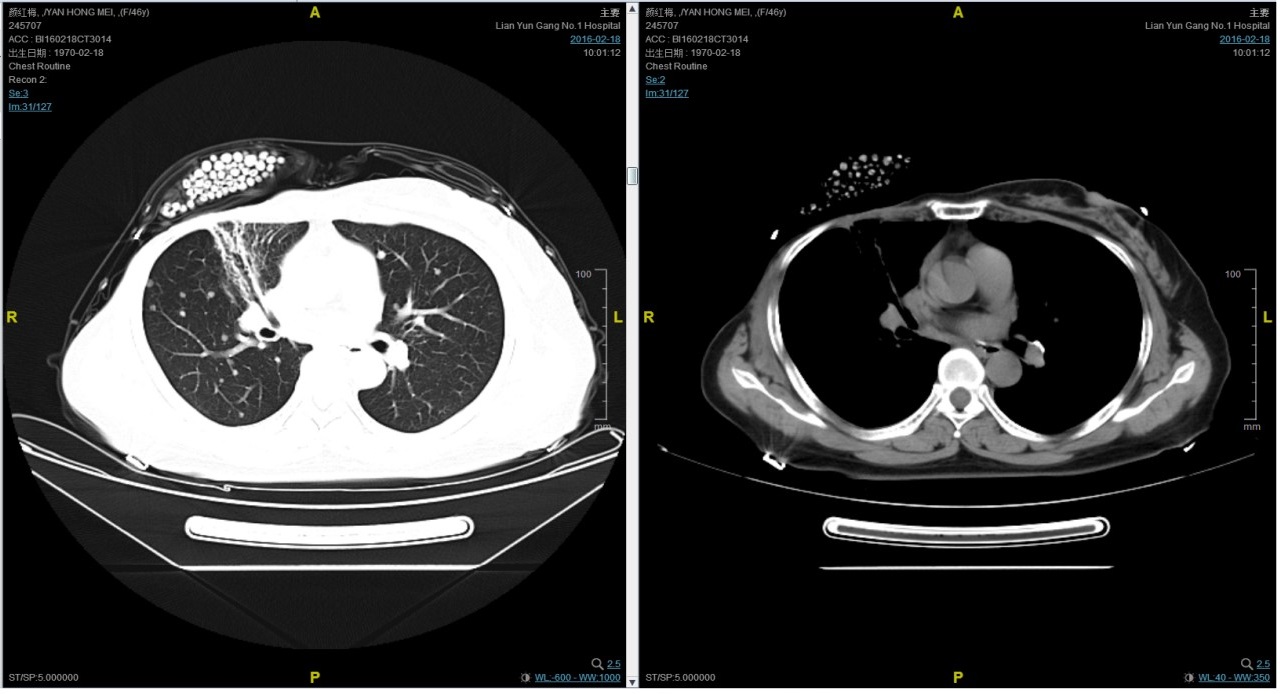

随访至2016-2-18,肺部病灶进展,肺内转移病灶增多。PFS2=10个月。

患者颜X X,女,发病年龄43岁。2010.12.01因体检发现右乳质硬、无痛性肿块住院治疗。入院查体肿块约2.5cm × 1.5cm。考虑诊断为右侧乳腺癌。2010.12.06在我院全麻下“右乳癌改良根治术”。术后病理:(右)乳腺浸润性导管癌,组织学分级Ⅲ级;乳头、皮肤未见癌累及,同侧腋窝淋巴结转移(19/19)。免疫组化:ER(-),PR(-),C- erbB-2(3+)。术后诊断右乳浸润性导管癌并右侧腋窝淋巴结转移(pT2N3M0,IIIC期,HER2阳性型)。术后于2011-01-06起在连云港市第一人民医院给予AC方案化疗4周期,2011-03-20给予右胸壁+右锁骨上下淋巴引流区放疗Dt50Gy/25f,2011-05-26予TH方案化疗4周期(曲妥珠单抗d1首次480mg,以后360mg)共4周期。后续予以曲妥珠单抗360mg(每21天为一周期)维持治疗1年,末次使用曲妥珠单抗的时间在2012年5月,后定期随访,病情稳定。2013-11-23全面复查发现肺转移。 DFS=35个月。2013-11-26起给予曲妥珠单抗(440mg d1)/脂质体紫杉醇(240mg d2)/CBP(500mg d2)方案化疗一个周期,出现Ⅱ度骨髓抑制,因患者主诉乏力明显,后修改方案曲妥珠单抗(330mg 每 3周重复)/脂质体紫杉醇(120mg d1+d8+d15,每4周重复)化疗,化疗过程顺利,患者无明显骨髓抑制,无乏力主诉,于2014-02-11全面复查,疗效评价为PR。继续曲妥珠单抗+脂质体紫杉醇(共六周期)治疗,疗效评价CR。后续予以曲妥珠单抗维持治疗,随访病情稳定。2015年4月,患者肺部病灶复发。给予曲妥珠单抗+希罗达治疗(希罗达1500mg,一天两次口服)。PFS1=17个月。2016-2-18,肺部病灶进展,肺内转移病灶增多。PFS2=10个月。从2016-2-19开始给予紫杉醇+曲妥珠单抗治疗,紫杉醇240mg,3周重复,曲妥珠单抗330mg三周重复。患者末次应用曲妥珠单抗和紫杉醇时间为2016-6-24,紫杉醇共应用4周期。CT评价SD。继续曲妥珠单抗维持治疗,且自服中药。2017-02-27患者因气喘胸闷再次就诊。患者肺部病灶进展,同时出现肝脏转移。再次给予曲妥珠单抗+长春瑞滨化疗一周期,效果不佳,患者放弃治疗。PFS3=12个月。